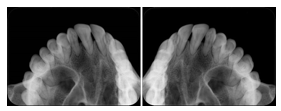

- OO-1. Intra-oral Full Mouth Series Structured Display